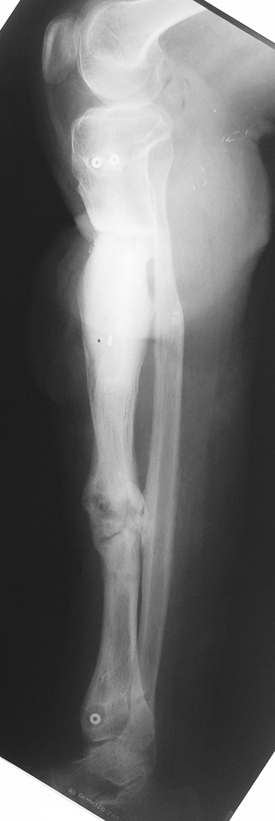

Recently, ilizarov techniques which is basis depend on distraction osteogenesis , bone segment transport or acute shortening after the resection at the site of pseudarthrosis combined with lengthening at another level of bone have been used. These treatment techniques may include some advantage for problems of infection, leg-length discrepancy, soft-tissue loss, and joint contracture.

Case 3